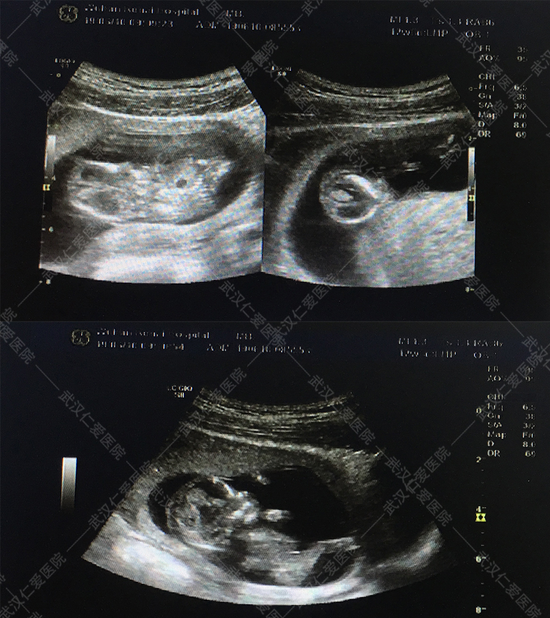

6月16號,武漢仁愛醫(yī)院NT篩查出兩例畸形胎兒,一例多器官多系統(tǒng)畸形,一例露腦畸形,這兩位孕媽都是孕12周+,其中一位還是高齡產(chǎn)婦今年33歲,喜懷二胎,本來是高高興興的來做產(chǎn)檢,沒想到NT篩查出胎兒露腦畸形。

露腦畸形

對于NT檢查,很多孕媽不是很了解,認(rèn)為和普通B超差不多,甚至還有一些孕媽覺得NT篩查可做可不做。武漢仁愛醫(yī)院超聲影像科王娟主任解釋:“NT篩查主要是通過B超檢查胎兒頸部透明層較厚的部位,用于早期診斷胎兒是否存在唐氏綜合征等染色體疾病及其他發(fā)育異常,很多孕媽沒等做四維彩超就被確診畸形的,所以這項檢查不容忽視。”